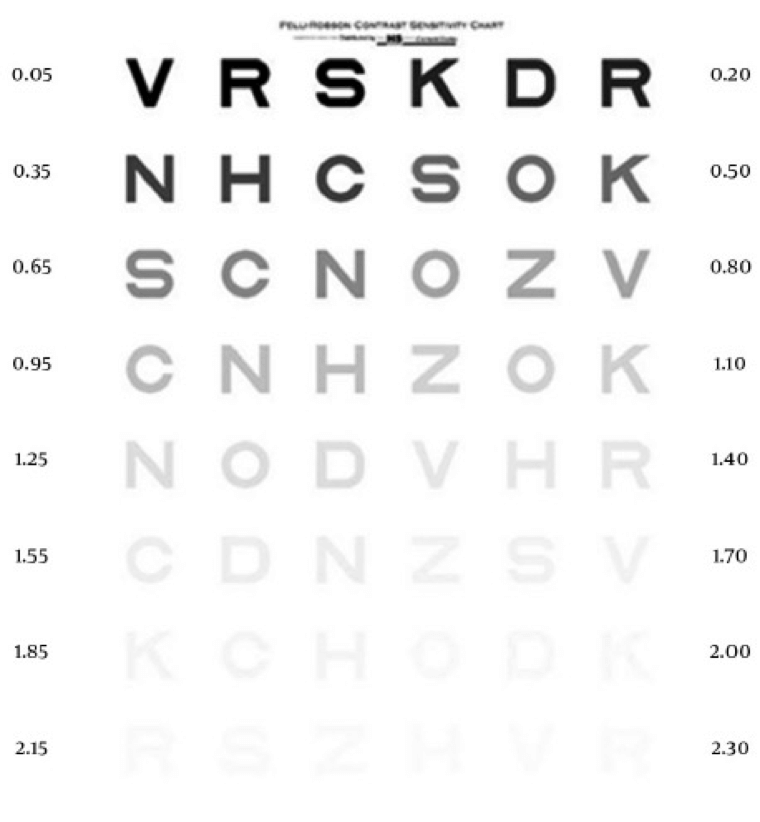

Untersuchung der Kontrastempfindlichkeit

Die Untersuchung der Kontrastempfindlichkeit verwendet die sog. Pelli-Robson-Tafel zur Prüfung der Kontrastempfindlichkeit. Diese Tafel verwendet Buchstaben gleicher Größe, die von hohem zu niedrigem Kontrast reichen.18 Je schwerer es für eine Person ist, die Buchstaben zu unterscheiden, desto niedriger wird ihre Kontrastempfindlichkeit eingestuft. Bei AMD helfen Untersuchungen der Kontrastempfindlichkeit, Sehstörungen zu erkennen, die bei einer Untersuchung der Sehschärfe möglicherweise nicht erkannt werden.19